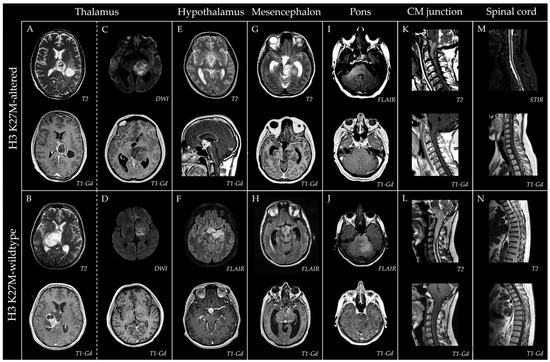

Prevalence and Clinicoradiopathological Characterization of H3 K27-Altered Diffuse Midline Gliomas in Adults—A Retrospective Observational Study

by Kristof Babarczy, Bence L. Radics, Lili Kiss, Alexandra Graczer, Bence Nagy, Sandor Dosa, Gyongyi Kelemen, Marton Balazsfi, Pal Barzo, Andras Voros, Peter Klivenyi and Levente Szalardy

Pathophysiology 2026, 33(1), 21; https://doi.org/10.3390/pathophysiology33010021 - 14 Mar 2026

Background/Objectives: Diffuse midline glioma (DMG), H3 K27M-altered, represents a rare group of gliomas arising in midline structures of the central nervous system. Historically regarded as a pediatric entity, it is now increasingly recognized in adults. Although its relative prevalence among all midline [...] Read more.

Background/Objectives: Diffuse midline glioma (DMG), H3 K27M-altered, represents a rare group of gliomas arising in midline structures of the central nervous system. Historically regarded as a pediatric entity, it is now increasingly recognized in adults. Although its relative prevalence among all midline diffuse gliomas and its clinical-radiological characteristics are well defined in children, these tumors remain less characterized in adults, and comparative evaluations with H3 K27 wildtype midline diffuse gliomas are limited. Methods: Consecutive adult patients with histopathologically confirmed diffuse glioma (WHO grade ≥ 2) diagnosed between 2016 and 2025 were retrospectively screened for midline tumor location, with systematic revision of imaging and pathology. For identified midline diffuse gliomas, comprehensive clinical, imaging, and immunohistochemical data were collected, and a detailed morphometric analysis was performed. H3 K27 alteration status was established immunohistochemically, with supplementary immunostaining when necessary. Descriptive and comparative analyses were conducted. Results: A total of 5% of the 541 adult diffuse gliomas were midline, and 23% of IDH wildtype midline gliomas were consistent with DMG, H3 K27-altered (all H3 K27M-mutant). The affected patients were significantly younger, and these tumors predominantly involved the thalamus and mesencephalon. Morphometric analyses revealed trends toward fewer high-grade features in H3 K27-altered tumors, with composite scores demonstrating significant discriminatory ability. The overall survival was not significantly different between groups but showed associations with ring-like enhancement as well as adjuvant and salvage therapies in the overall midline cohort. Conclusions: This study provides population-based prevalence estimates for DMG, H3 K27M-altered, and complements the limited literature with comparative clinical-radiological and morphometric data of potential prognostic relevance. Full article